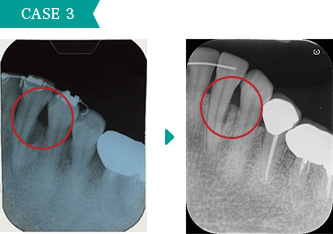

重度の歯周病の状態で歯茎も腫れて動いている歯もありましたので、全体的に歯周外科処置を行いました。歯周病の改善がみられます。